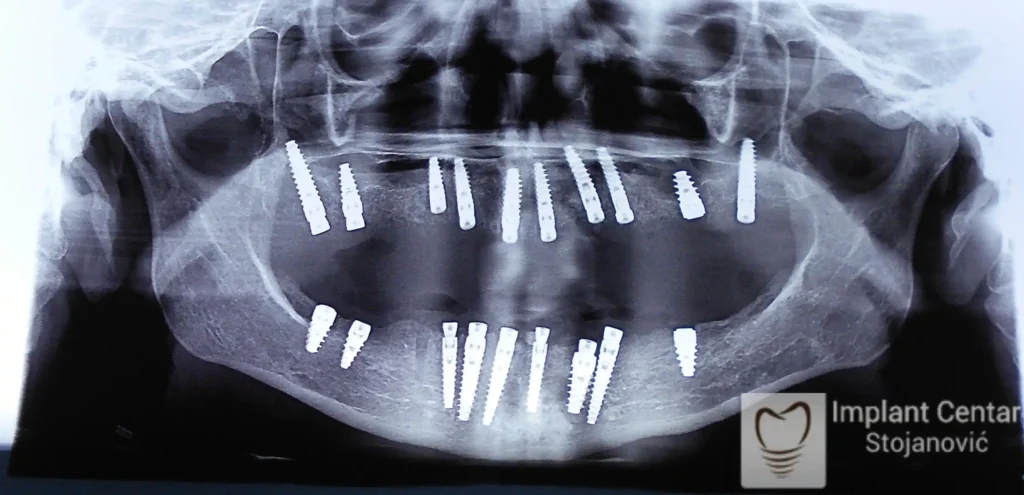

Na slici 1. i slici 2. prikazan je izgled pacijenta pre početka terapije – klinički i rendgenološki.

Nakon vađenja zuba, ugrađeni su implantati. Na slici 3 prikazan je ortopan snimak sa ugrđenim implantatima. Tokom perioda osteointegracije, pacijent je bio zbrinut fiksnim privremenim krunicama na implantatima, koje su izrađene samo dva dana nakon hirurške intervencije.

Na slikama 5. i 6. prikazan je izgled definitivnih cirkonijum-keramičkih mostova na implantatima.